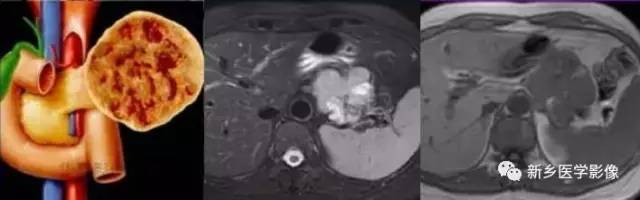

2、影像学诊断:

CT 、M RI 上, 本病表现为胰腺边界清楚的大肿块, 囊实相间, 实性部分主要位于病变周边,有强化;囊性部分主要位于病灶中心区域, 囊变区密度较高, CT 值40 ~50Hu 。30 %的患者病变周边可见钙化。

由于病变内常有出血,T1W I 上可见不均匀高信号, T 2WI 上见不均匀低信号 。M RCP 或E RCP 示胰管受压、移位或中断。